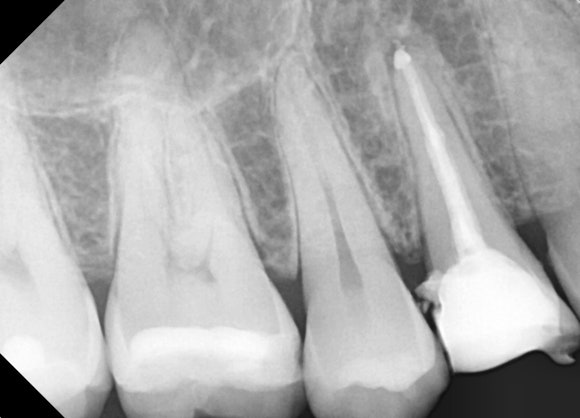

20250329

혼자서만 색깔이 다른 치아가 보이시지요?

치아 깨진 공간으로 잇몸들이 자라들어올 정도이니

얼마나 오랫동안 방치되었는지 알 수 있습니다.